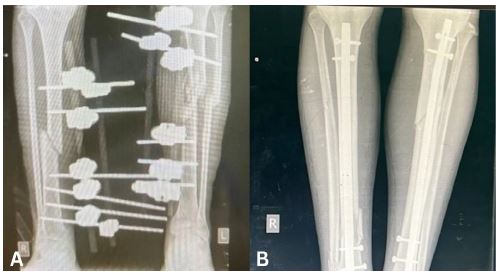

A 23-year-old female was admitted to the Emergency Department (ED) with an isolated Gustilo IIIB open fracture of the right tibia after a neighbouring house was bombed (Figure 1A). She was resuscitated in the ED, given IV Ceftriaxone antibiotics and underwent irrigation and debridement of the wound. She was taken to theatre within 12 hours for proper wound debridement, Intramedullary Nail (IMN) fixation (Figure 1B) and wound coverage with a local flap and Split-skin thickness Skin Graft (SSG). Her post-operative course was uneventful and the wound was found to be healed within three weeks. She was subsequently allowed to mobilise with partial weight-bearing.

Figure 1: (A) Anteroposterior view radiograph of the right leg showing comminuted fractures of the tibia and fibula. (B) Anteroposterior view radiograph of the right leg with intramedullary nail fixation of the fracture.

An 18-year-old male presented with fractures sustained during a bombing. He had been found under the rubble of a collapsed house after the incident. He sustained a Gustilo-Anderson Grade II open fracture of the proximal tibia on the left and a closed fracture of distal tibia on the right. There was also a fibular fracture on the left. At the time of his first presentation, soft tissue was repaired and external fixators were used to stabilise the fractures on both sides. These were in place for 14 weeks during which the patient was non-weight bearing and completely bed-bound. After 14 weeks, there was no sign of bone healing on radiography (Figure 5A). Plans were made for external fixators to be removed. Due to a lack of resources and time constraints, external fixators needed to be removed and IMN fixation inserted immediately afterwards during the same session (Figure 5B). To prepare for this, he was started on a regimen of IV Ceftriaxone 48 hours prior to the removal of the external fixators. The patient began weight-bearing as tolerated 2 days after intramedullary nailing. Wounds were found to have healed two weeks after intramedullary nailing, a total of 16 weeks after his initial presentation.

Figure 5: (A) Anteroposterior view radiograph of both legs showing external fixators in situ. (B) Anteroposterior view radiograph of both legs showing intramedullary nails in situ.